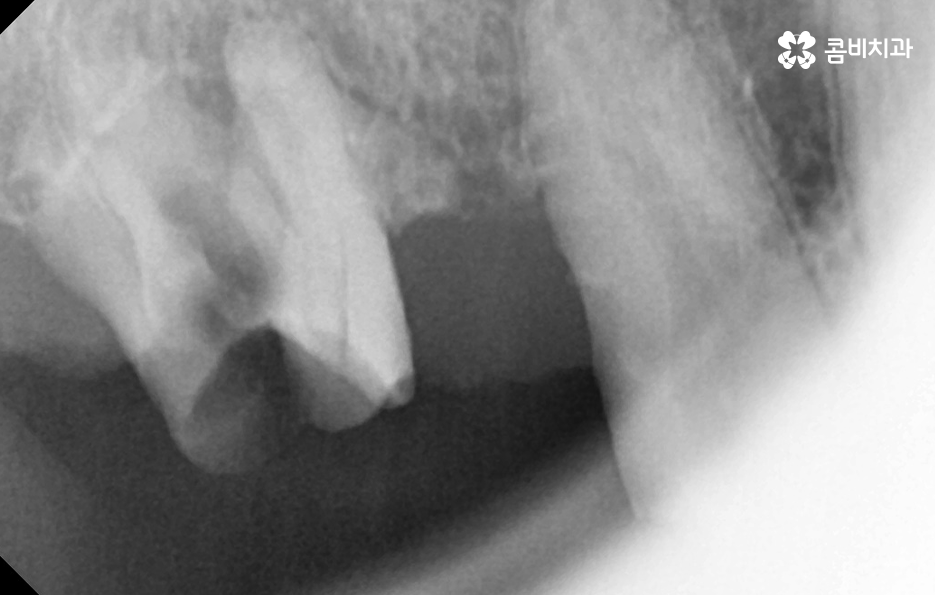

노년기에 치아 상실이 증가하는 큰 원인은 치주염의 장기적 누적 효과로서 치주염은 잇몸 염증이 잇몸뼈까지 파고들어 뼈를 녹여 치아를 지탱하지 못하게 만드는 병으로 젊을 때는 잇몸이 어느 정도 회복되기 때문에 크게 느껴지지 않지만, 나이가 들수록 회복 속도는 느려지고 염증은 더 빨리 확산되며 잇몸뼈가 한 번 녹기 시작하면 다시 원래 그대로 회복되는 것은 사실상 어렵기 때문에 치아는 점점 흔들리고, 결국 발치까지 이어질 수 있어요

그리고 충치 재발 또는 오래된 보철물의 노후화 문제도 큰데 젊은 시절 충치 치료나 크라운, 브릿지 등을 했더라도 노년이 되면 재 치료가 필요한 경우가 많으며 보철물은 영구적이지 않기 때문에 접착력이 약해지거나 잇몸이 내려가면서 보철물 경계부위에 충치가 다시 생길 수 있고 특히 치아 뿌리 부분에 생기는 충치는 진행 속도가 빨라 치료가 어려운 경우도 많아서 보철물 아래 치아가 불안정해지면 결국 발치해야 하는 상황이 생기는 거예요.